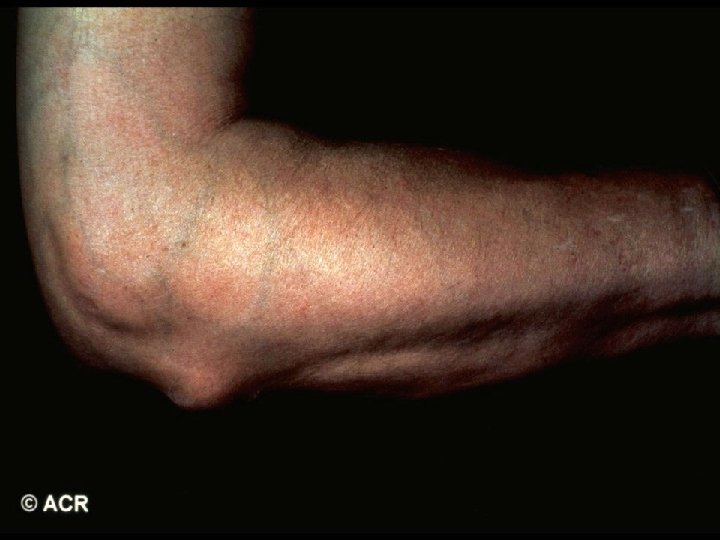

· In addition to steroid therapy, several different disease-modifying drugs were given over the years since diagnosis, including sulfasalazine, oral gold, chloroquine, methotrexate, and TNFinhibitors. · A total of 16 orthopedic operations had been performed including excision of rheumatic nodules, tendon repair, and bilateral knee- and unilateral hip-replacement.

· On exam, he showed signs of extensive rheumatoid arthritis, most marked on hand, foot, and shoulder joints as well as rheumatic nodules on both elbows. · HR regular at 105/min · BP 130/90 mm Hg · ESR 82 mm/h

ACR 1987 Classification Criteria For Rheumatoid Arthritis Patients Must have Four of Seven Criteria Morning Stiffness Lasting at Least 1 Hour* Swelling in 3 or More Joints* Swelling in Hand Joints* Symmetric Joint Swelling* Erosions or Decalcification on X-Ray of Hand Rheumatoid Nodules Abnormal Serum Rheumatoid Factor * Must Be Present at Least 6 Weeks

Prognostic Markers in RA · Early Markers - Generalized onset with numerous joints involved - Systemic involvement including fatigue, fever, weight loss, morning stiffness - Elevated CRP or ESR - Positive test for rheumatoid factor/Anti. CCP - Early erosions, JSN - HLA-DR 4 genetic marker

Prognostic Markers in RA · Definitive Markers - Subcutaneous nodules - Detection of erosions on x-ray